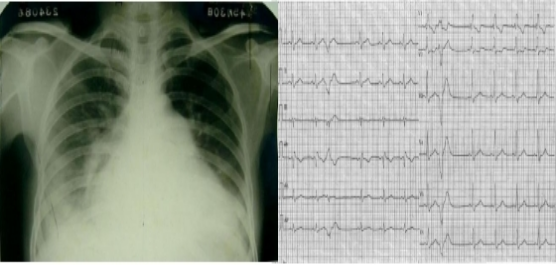

慢型克山病典型X线表现 慢型克山病心电图表现